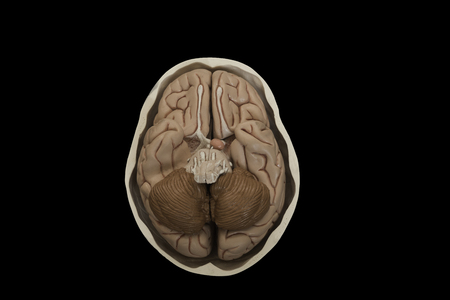

Brain samples preserved in plastic slides, coronal section.

Base of human brain model in the skull model isolated on black background